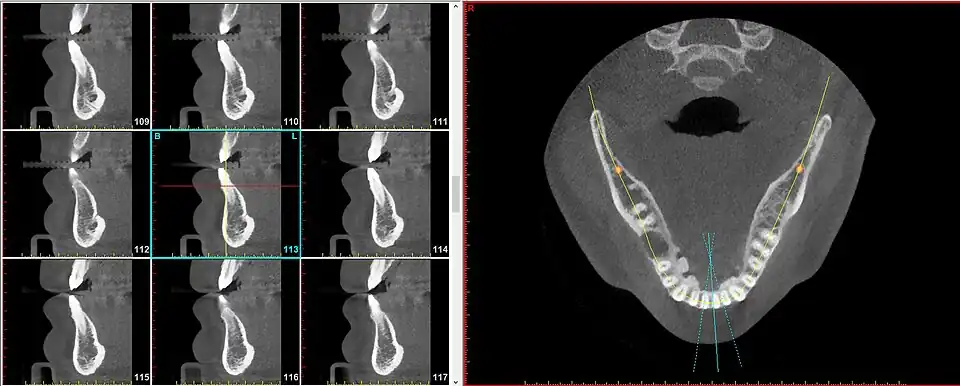

A radial plane is an anatomical plane that is used to describe a virtual slice along a radius of a somewhat cylindrical shaped body part.[1] The radial planes need not be perfectly drawn to overlap on an exact intersection point, particularly when the body part being sectioned is not a perfect cylinder, such as in the case of the maxilla and mandible.

The radial plane can be useful because certain anatomical elements repeat in a circumferential manner (such as around the curvature of the dental arch (i.e. the jaw) and to speak of these entities using parallel planes becomes cumbersome and inaccurate.

For instance, the segment of bone on the outer circumference of each individual tooth is referred to as the facial plate of bone. Because the facial plate of bone is anterior to the incisors (in the front of the mouth) but lateral to the premolars and molars (in the back of the mouth), to visualize the facial plate of bone on various teeth will require sagittal slices for the former but coronal slices for the latter. To achieve greater uniformity and diminished confusion, simply speaking of radial slices provides a satisfactory solution for all teeth in both (upper and lower) arches.